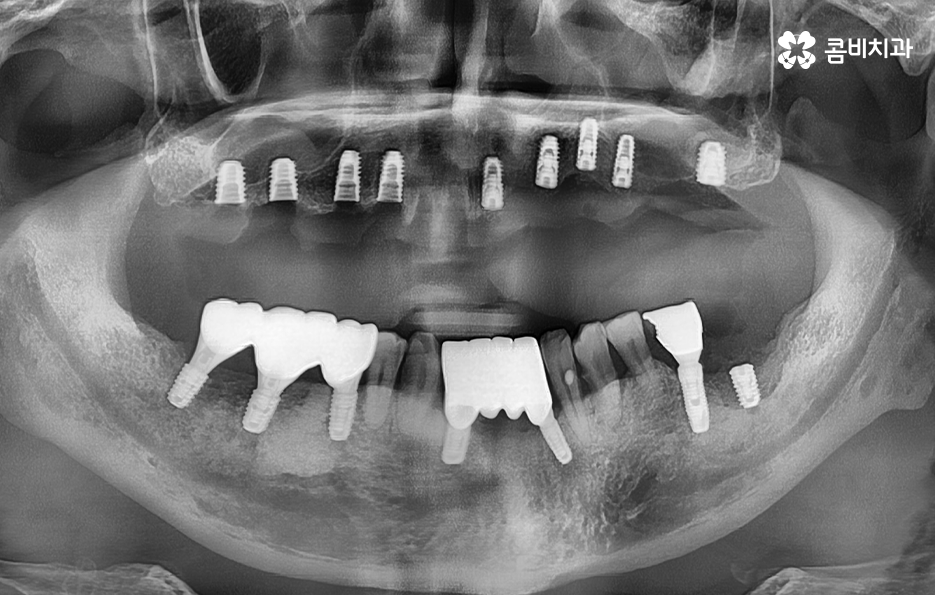

위 환자분의 케이스는 치주염이 심해져서 치아를 잃게 되기도 했지만 윗니의 경우 브릿지로 치아 기능을 유지하다가 결국 임플란트를 하게 된 사례로 볼 수 있어요

과거에는 임플란트 치료 자체가 없어서 브릿지나 틀니와 같은 치료를 할 수 밖에 없었지만 브릿지와 틀니의 한계점은 치아의 기능적인 부분에서도 한계점이 분명하지만 그에 더해 치조골이 점점 내려 앉고 흡수된다는 점에서도 임플란트의 장점이 명확하다고 할 거예요

치아 상실 후 잇몸을 그대로 방치하는 기간이 길어질수록 잇몸 뼈의 흡수로 인해 뼈이식의 양이 늘어나고 시술 기간이 더 길어질 수 있으니 무작정 참지 마시고 임플란트 시술은 나이가 아니라 잇몸 뼈의 상태가 더 중요하다는 점을 감안하여 꼭 늦지 않게 치과에 방문하시길 바라고 있어요